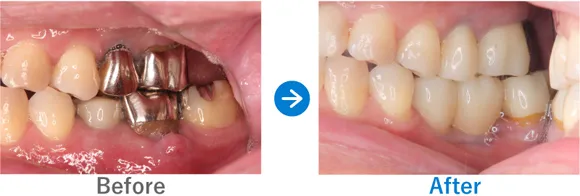

Case2

ブリッジで両隣の歯もダメに…。インプラント治療後は奥歯でしっかり噛めるように!

右下7はかなり前に抜歯後、ブリッジ治療済み。左下6は抜歯後、義歯を入れたがほとんど使っていない

インプラント4本:右下6・7、左下6・7

1,249,500円(内訳:GBR、インプラント4本(ネオデント)、ガイド、仮歯、セデーション、骨補填材、保証20年)

来院の背景

下顎の左右の臼歯部がブリッジによる影響で傷んでしまい、義歯に変更したもののほとんど使えない状態でした。奥歯で噛めないことにストレスを感じ、インプラントを検討。先にインプラント治療をしていた奥様からの紹介で来院されました。

治療結果

来院時の検査で、骨はやせてはいたものの治っている状態だったので、インプラント埋入と同時に骨補填をし、下顎の左右に2本ずつインプラントを埋入し治療完了しました。しっかり噛めるようになり患者様も喜んでおられます。今後はナイトガードを使用して、ブラキシズム(無意識下の歯ぎしり、食いしばりなど)の予防をしていく予定です。